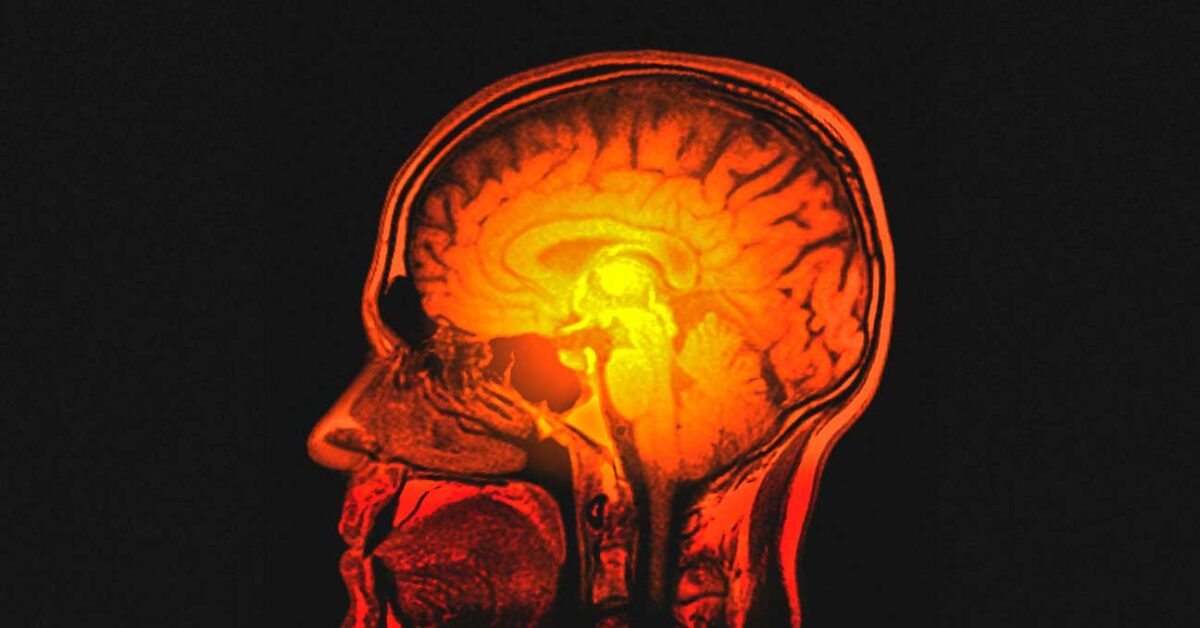

თავის ტვინის შეშუპება მოსალოდნელია ეპილეფსიური შეტევის, სისხლის დაავადებისა და ენდოკრინული დარღვევების დროს

თავის ტვინის შეშუპება შეიძლება განვითარდეს მრავალი ისეთი დაავადების ფონზე, რომელიც ნერვული სისტემის დაზიანებით მიმდინარეობს. ასეთია, უპირველეს ყოვლისა, თავის ტვინის სისხლის მიმოქცევის მწვავე დარღვევა და ქალა-ტვინის ტრავმა. შემდეგ უნდა მოვიხსენიოთ ინფექციური დაავადებები, ინტოქსიკაციები, ჰიპოქსია, თავის ტვინის სიმსივნე, ალერგია, დიდხანს მიმდინარე სომატური (გულ-სისხლძარღვთა და სასუნთქი ორგანოების) დაავადებები, ოპერაციული ჩარევის შემდგომი მდგომარეობები.

თავის ტვინის შეშუპება მოსალოდნელია აგრეთვე ეპილეფსიური შეტევის დროს, სისხლის დაავადების, ენდოკრინული დარღვევის ფონზე, მაიონიზებელი რადიაციის ზემოქმედების შემთხვევაში.